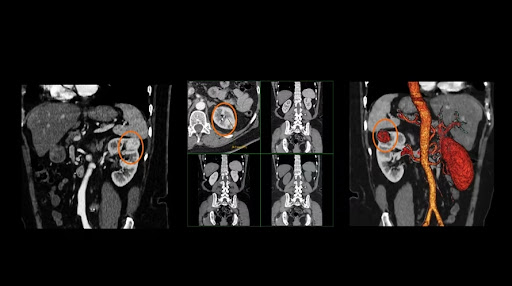

1. Опухоль почки в 4 фазах (10,1 м3в)